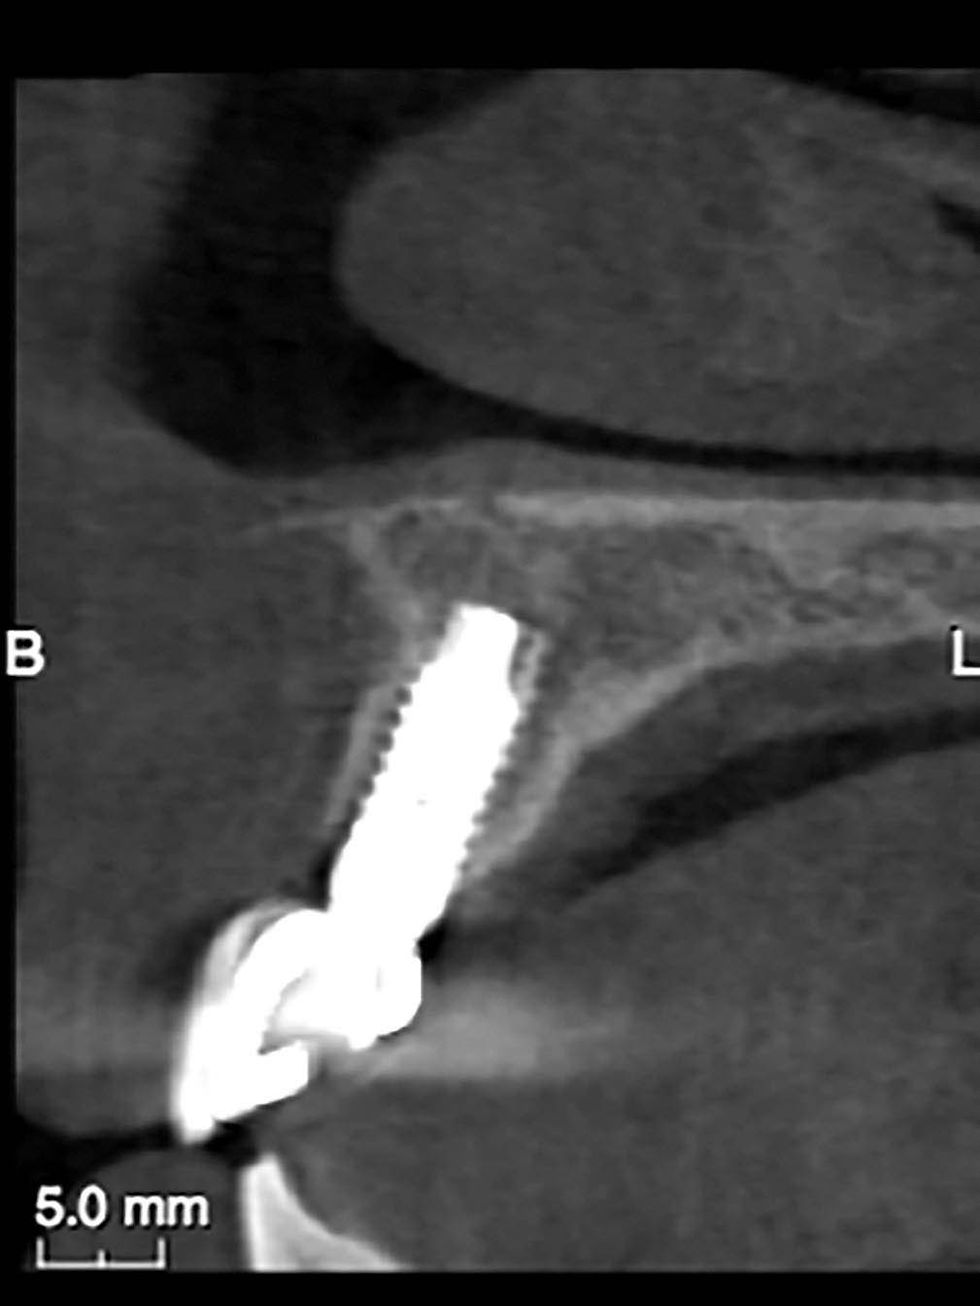

Lateral image after the planning: the software allows the implant to be positioned by verifying the correct prosthetic emergence and angle in respect of the vestibular wall.

The implant is inserted through the surgical template, according to the established angle and depth.

The mechanical stop of the mounter onto the template sleeve places the fixture congruently to the planning.

Radiographic control after surgery.

Control CBCT at 36 months: the intact vestibular wall can be appreciated.